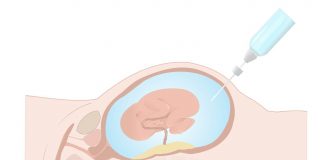

Amniyosentez Tarihe mi Karışıyor?

Gebelik

Uzm. Dr. Anıl Yeşildal